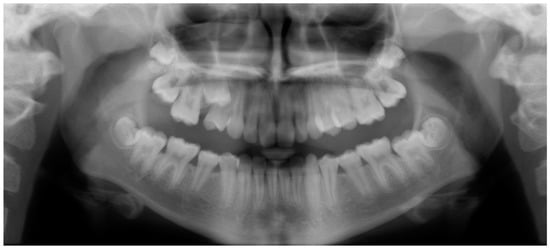

- Evaluation of buccal and lingual cortical plates: Figure 5, Figure 6 and Figure 7 show a case in which the mandibular lateral incisors are positioned lingual to the central incisors. Both mandibular lateral incisors are adjacent to each other. Figure 5 shows and intraoral occlusal photos with retained deciduous mandibular lateral incisors. There was no way to evaluate the buccal and lingual cortical plates through conventional 2D panoramic, periapical or occlusal radiographs. Therefore, CBCT was acquired and collimated to the area of teeth in order to assess the relationship of the four mandibular incisors to the labial and lingual cortical plates as well as to the adjacent teeth. As Figure 6 and Figure 7 display, CBCT shows that all permanent mandibular incisors are sound. It is important to note that thin buccal and lingual cortical plates may not be seen via CBCT—this does not denote that they are not present. In other words, CBCT images may not show a clinically present thin buccal and lingual cortical plates. In this case, the diagnostic information obtained from CBCT is far more significant than the information obtained from any other radiographic imaging technique.